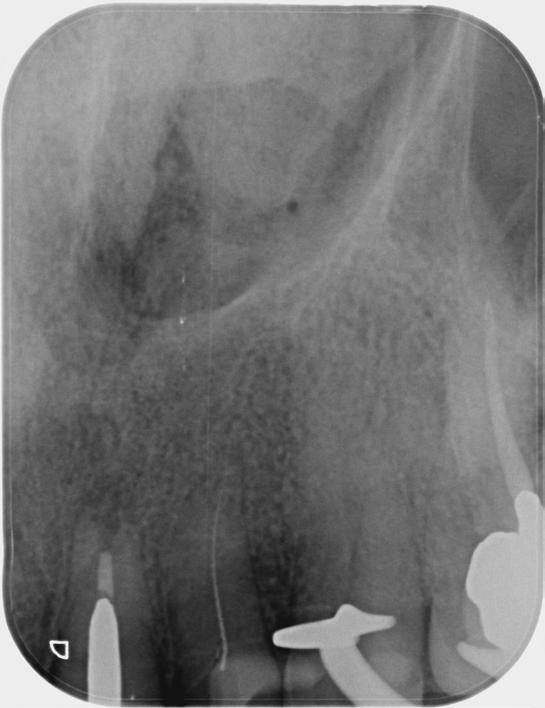

Based on the clinical and radiographic findings, tooth 22 was diagnosed as necrotic with a possibly infected root canal system (RCS), pulp canal calcification and primary acute apical periodontitis due to decay, cracks and restoration breaking down. An endodontic investigation procedure was planned to determine whether the 22 was suitable for further restoration. While the treatment was supposed to be straightforward initially, it progressed to become very complex surprisingly. This was due to separation of a size-10 H-file in the root canal of tooth 22.

The instrument separation was first noticed after taking the initial radiograph to establish the working length. It probably happened due to the patient biting inadvertently on the file during x-ray exposure. As our patient was a bruxer, his bite forced the file deeper in the

severely calcified root canal. The file was now firmly stuck inside the root canal. Despite trying to gently retrieve the file, it broke at junction of the cutting surface to the shank. Bypassing and/or retrieval procedures were planned and performed by using hand files, rotary files and Satelec ultrasonic tips in three different sessions, each one almost three hours long. Rotary files were used mainly as adjunctive instruments.

Taking advantage of rotary files made of a heat-treated alloy with minimal cutting efficiency, designed in a way to scrape rather than cut the dentin, enabled me to safely enlarge the space made by the hand files. This technique also participated in less frequency and chance of breaking more files next to the broken file.

Finally, the broken file segment was removed with braiding barbed broaches around the file. Notably, the patient patiently cooperated all throughout the treatment.

I had a thorough discussion with the patient about the reasons why this incident happened. Even though I could have simply pointed out a severely calcified root canal or a heavy bite to be responsible for the incident, I concluded that the patient’s occlusion should have been assessed carefully during case assessment in order to set preventive measures, which in turn could have potentially saved the patient and I from all the consequences.

Take home message - ALWAYS check your patient’s occlusion during the first examination/ consultation session. It will save you a lot of money!

Fig.1 File got stuck (22/09/2023) Fig.2 File fractured (22/09/2023)

Fig.4 Cut the file deeper (22/09/2023)

Bypassed to WL (12/10/2023)

And even deeper (12/10/2023)

Fig.3 Made space coronally (22/09/2023)

Fig.6 Rotary files used (12/10/2023)

Fig.8 Finally retrieved the file (12/10/2023)